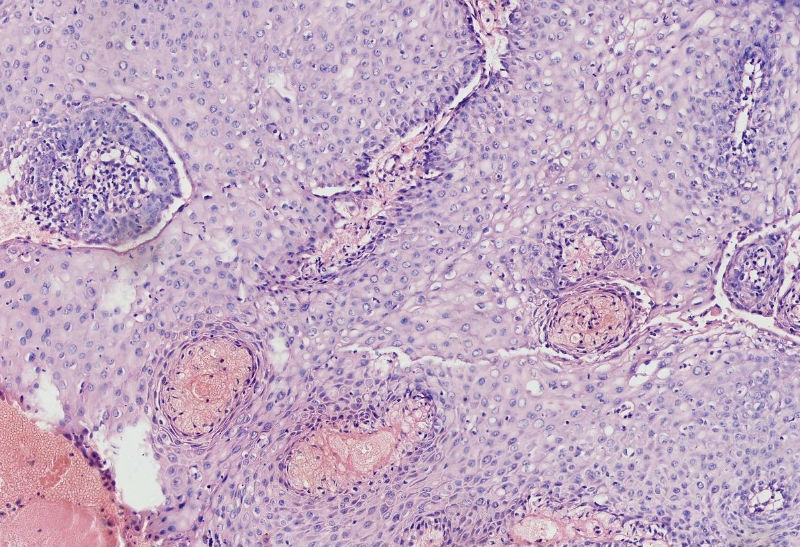

女45岁,宫颈口可见一突出物直径约0.5菜花状质脆

图3

细胞异型性不太大,考虑湿疣样增生

CIN3,伴湿疣感染

细胞异型不大,乳头状瘤。

乳头状的CIN,有平切,似乎有高级别的CIN,需除外癌。